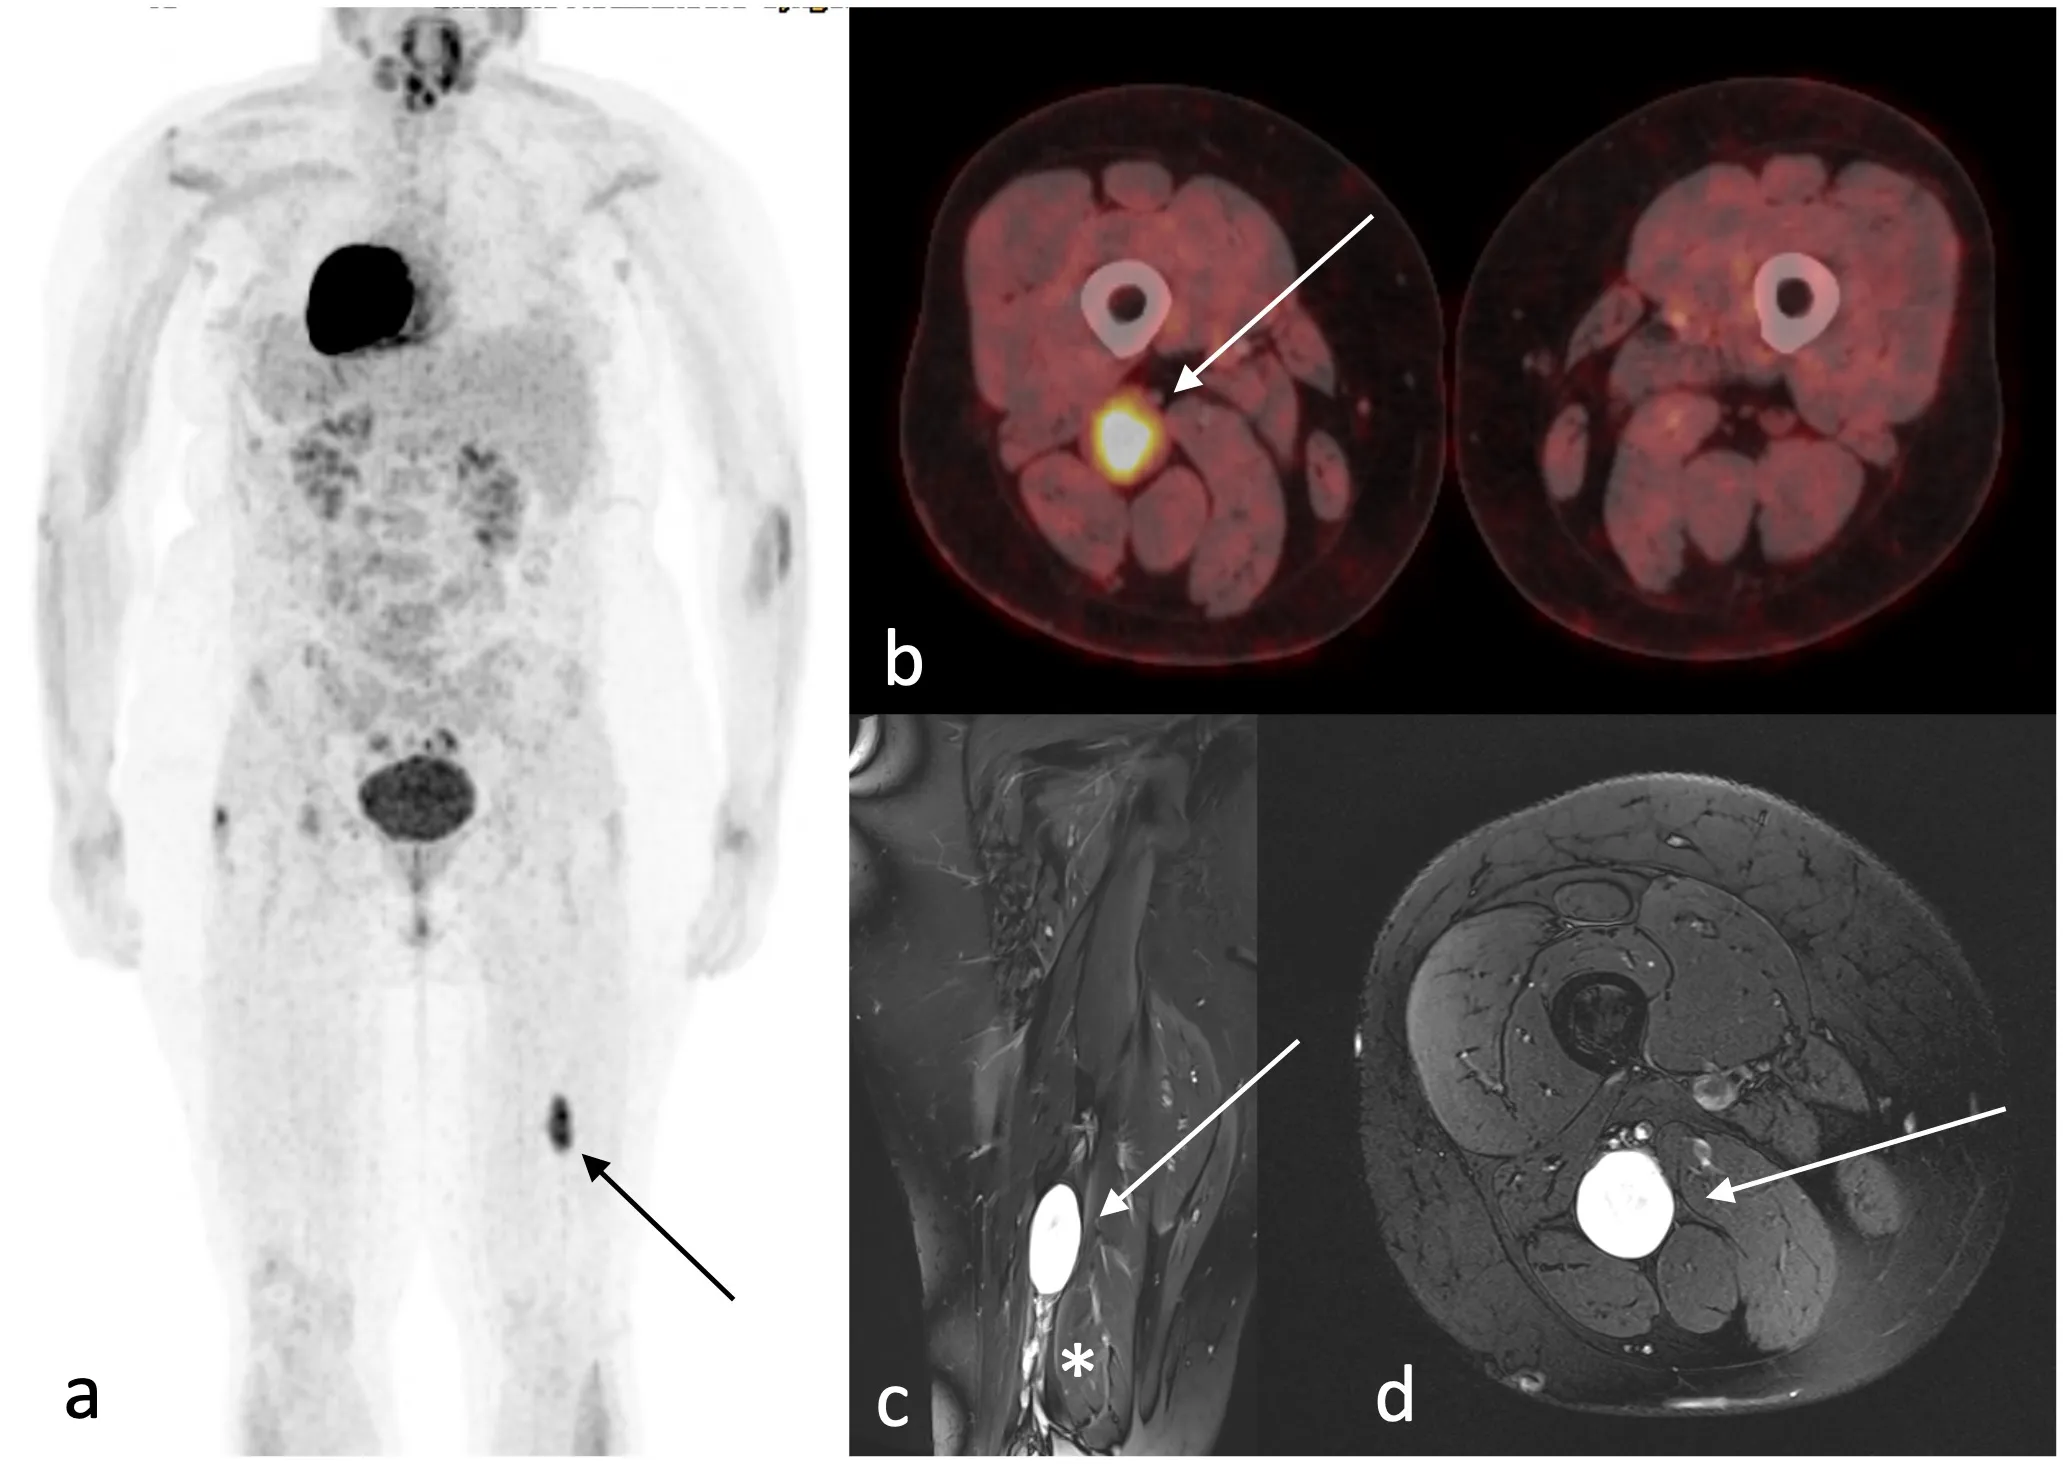

4.2 PET/TC con FDG

- 🩻 Puede ayudar a seleccionar la lesión o la zona más sospechosa para biopsia.

- 🩻 No sustituye a la histología.

- 🩻 Debe interpretarse junto con la RM y el contexto clínico.

4.3 Mensaje práctico

La imagen no suele ser suficiente para separar ANNUBP de MPNST con seguridad absoluta; su mayor valor práctico está en detectar transformación sospechosa y orientar la biopsia.